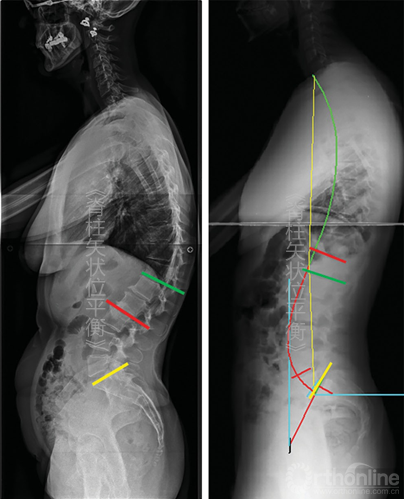

这种功能分段同样可在胸椎应用。脊柱前凸区域与后凸区域之间的关系是上凸区域与后凸区域之间的一种平等关系(图5-9)。

图5-9 根据Berthonnaud等的脊柱分段 CC.颈椎弯曲;SS.骶骨倾斜;TC.胸椎弯曲

由于LL在解剖学和功能上的定义可能存在混淆,所以建议LL描述为T12~L1间隙同骶骨上终板之间的弯曲,而骶骨上终板同拐点之间的弯曲作为脊柱远端前凸(distal spinal lordosis,DSL)(图5-10)。在第一种情况下,定义LL只需要一个角度;第二种情况下,需要一个角度和椎体数量去测量角度(图5-10)。

图5-10对比传统腰椎前凸定义和新的脊柱远端前凸角(DSL)

注意前凸弧的长度,黄线为S1上终板,绿线为L1上终板,红色弧线表示DSL。图示的2种情况下,2个DSL存在显著的生物力学差异(左图DSL较小,右侧较大)

在脊柱颈胸段也同样可以用弯曲顶点进行分段:胸椎后凸则定义为在两个拐点之间的弯曲,颈椎前凸定义为从C3至近端拐点之间的弯曲。因为成像技术(数字影响或EOS系统)已经能清晰的辨认T1椎体,T1椎体上终板的方向便有了更重要的意义。T1倾斜角即为T1上终板同水平线之间的夹角,其对理解颈椎弯曲方向有着重要的意义。

在功能性脊柱分段中,胸椎后凸形态与远端脊柱前凸形态相互影响。首先当胸椎后凸累及椎体长度增加时,远端脊柱前凸形态减小,反之亦然;其次角度方面,胸椎后凸的下弧角等于远端脊柱前凸的上弧角。